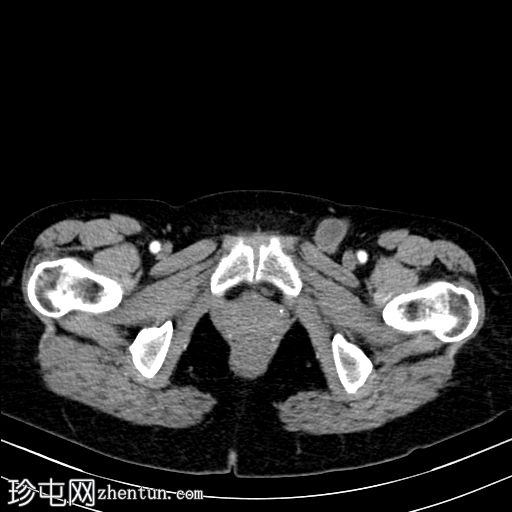

CT

轴位增强扫描

动脉期

左侧股疝,疝内容物包含大部分输卵管和卵巢。卵巢静脉也可追踪至疝囊内,证实卵巢也位于疝囊内。

子宫向左侧股管方向移位。